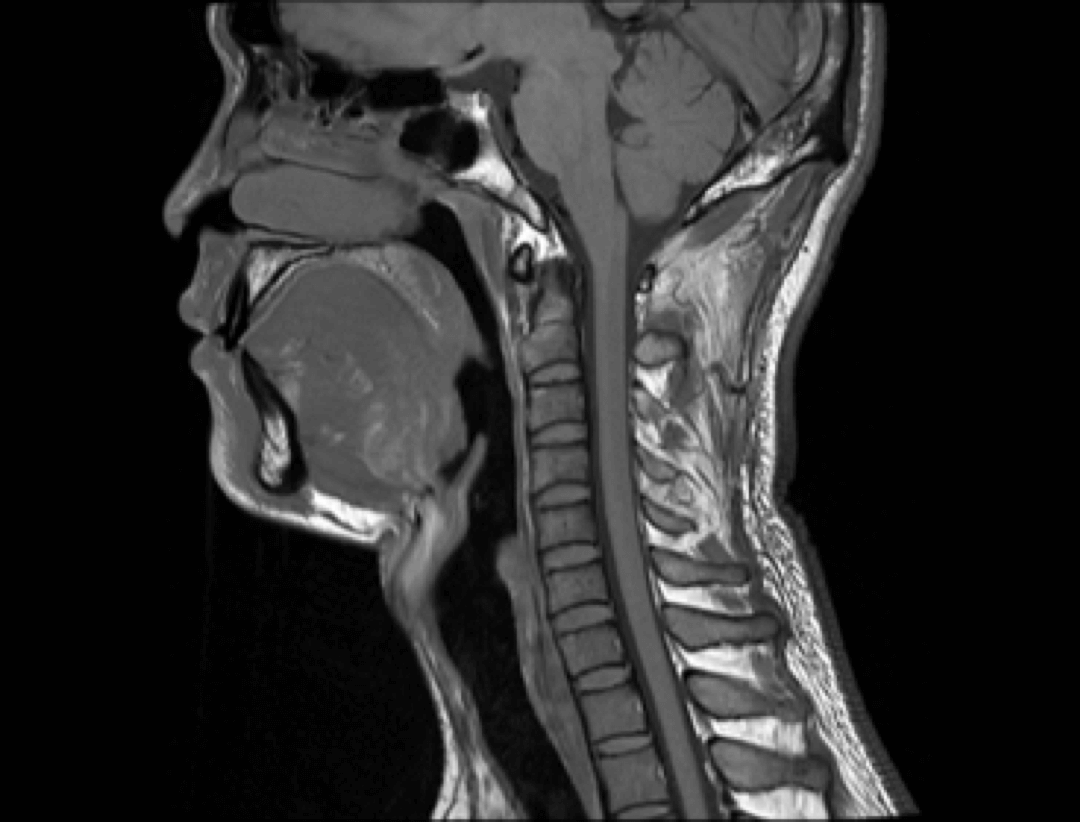

Neuro

Spine